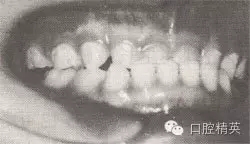

患者,男,4歲,乳牙。磨牙近中關(guān)系。前牙反頜,下頜前突,位置前移。

診斷:乳前牙反頜,安氏Ⅲ類,毛氏Ⅱ¹。

矯治設(shè)計(jì):上頜頜墊式活動矯治器。下頜后退位解剖式頜墊,舌簧推乳上切牙向唇側(cè),調(diào)磨頜墊。

治療時(shí)間:1.5個(gè)月,乳前牙反頜解除,乳切牙達(dá)到正常覆頜、覆蓋。下頜回到正常位置。

圖8-37 安氏Ⅲ類錯(cuò)頜,乳前牙反頜矯治前后面頜像

矯治前面相

矯治前咬合圖